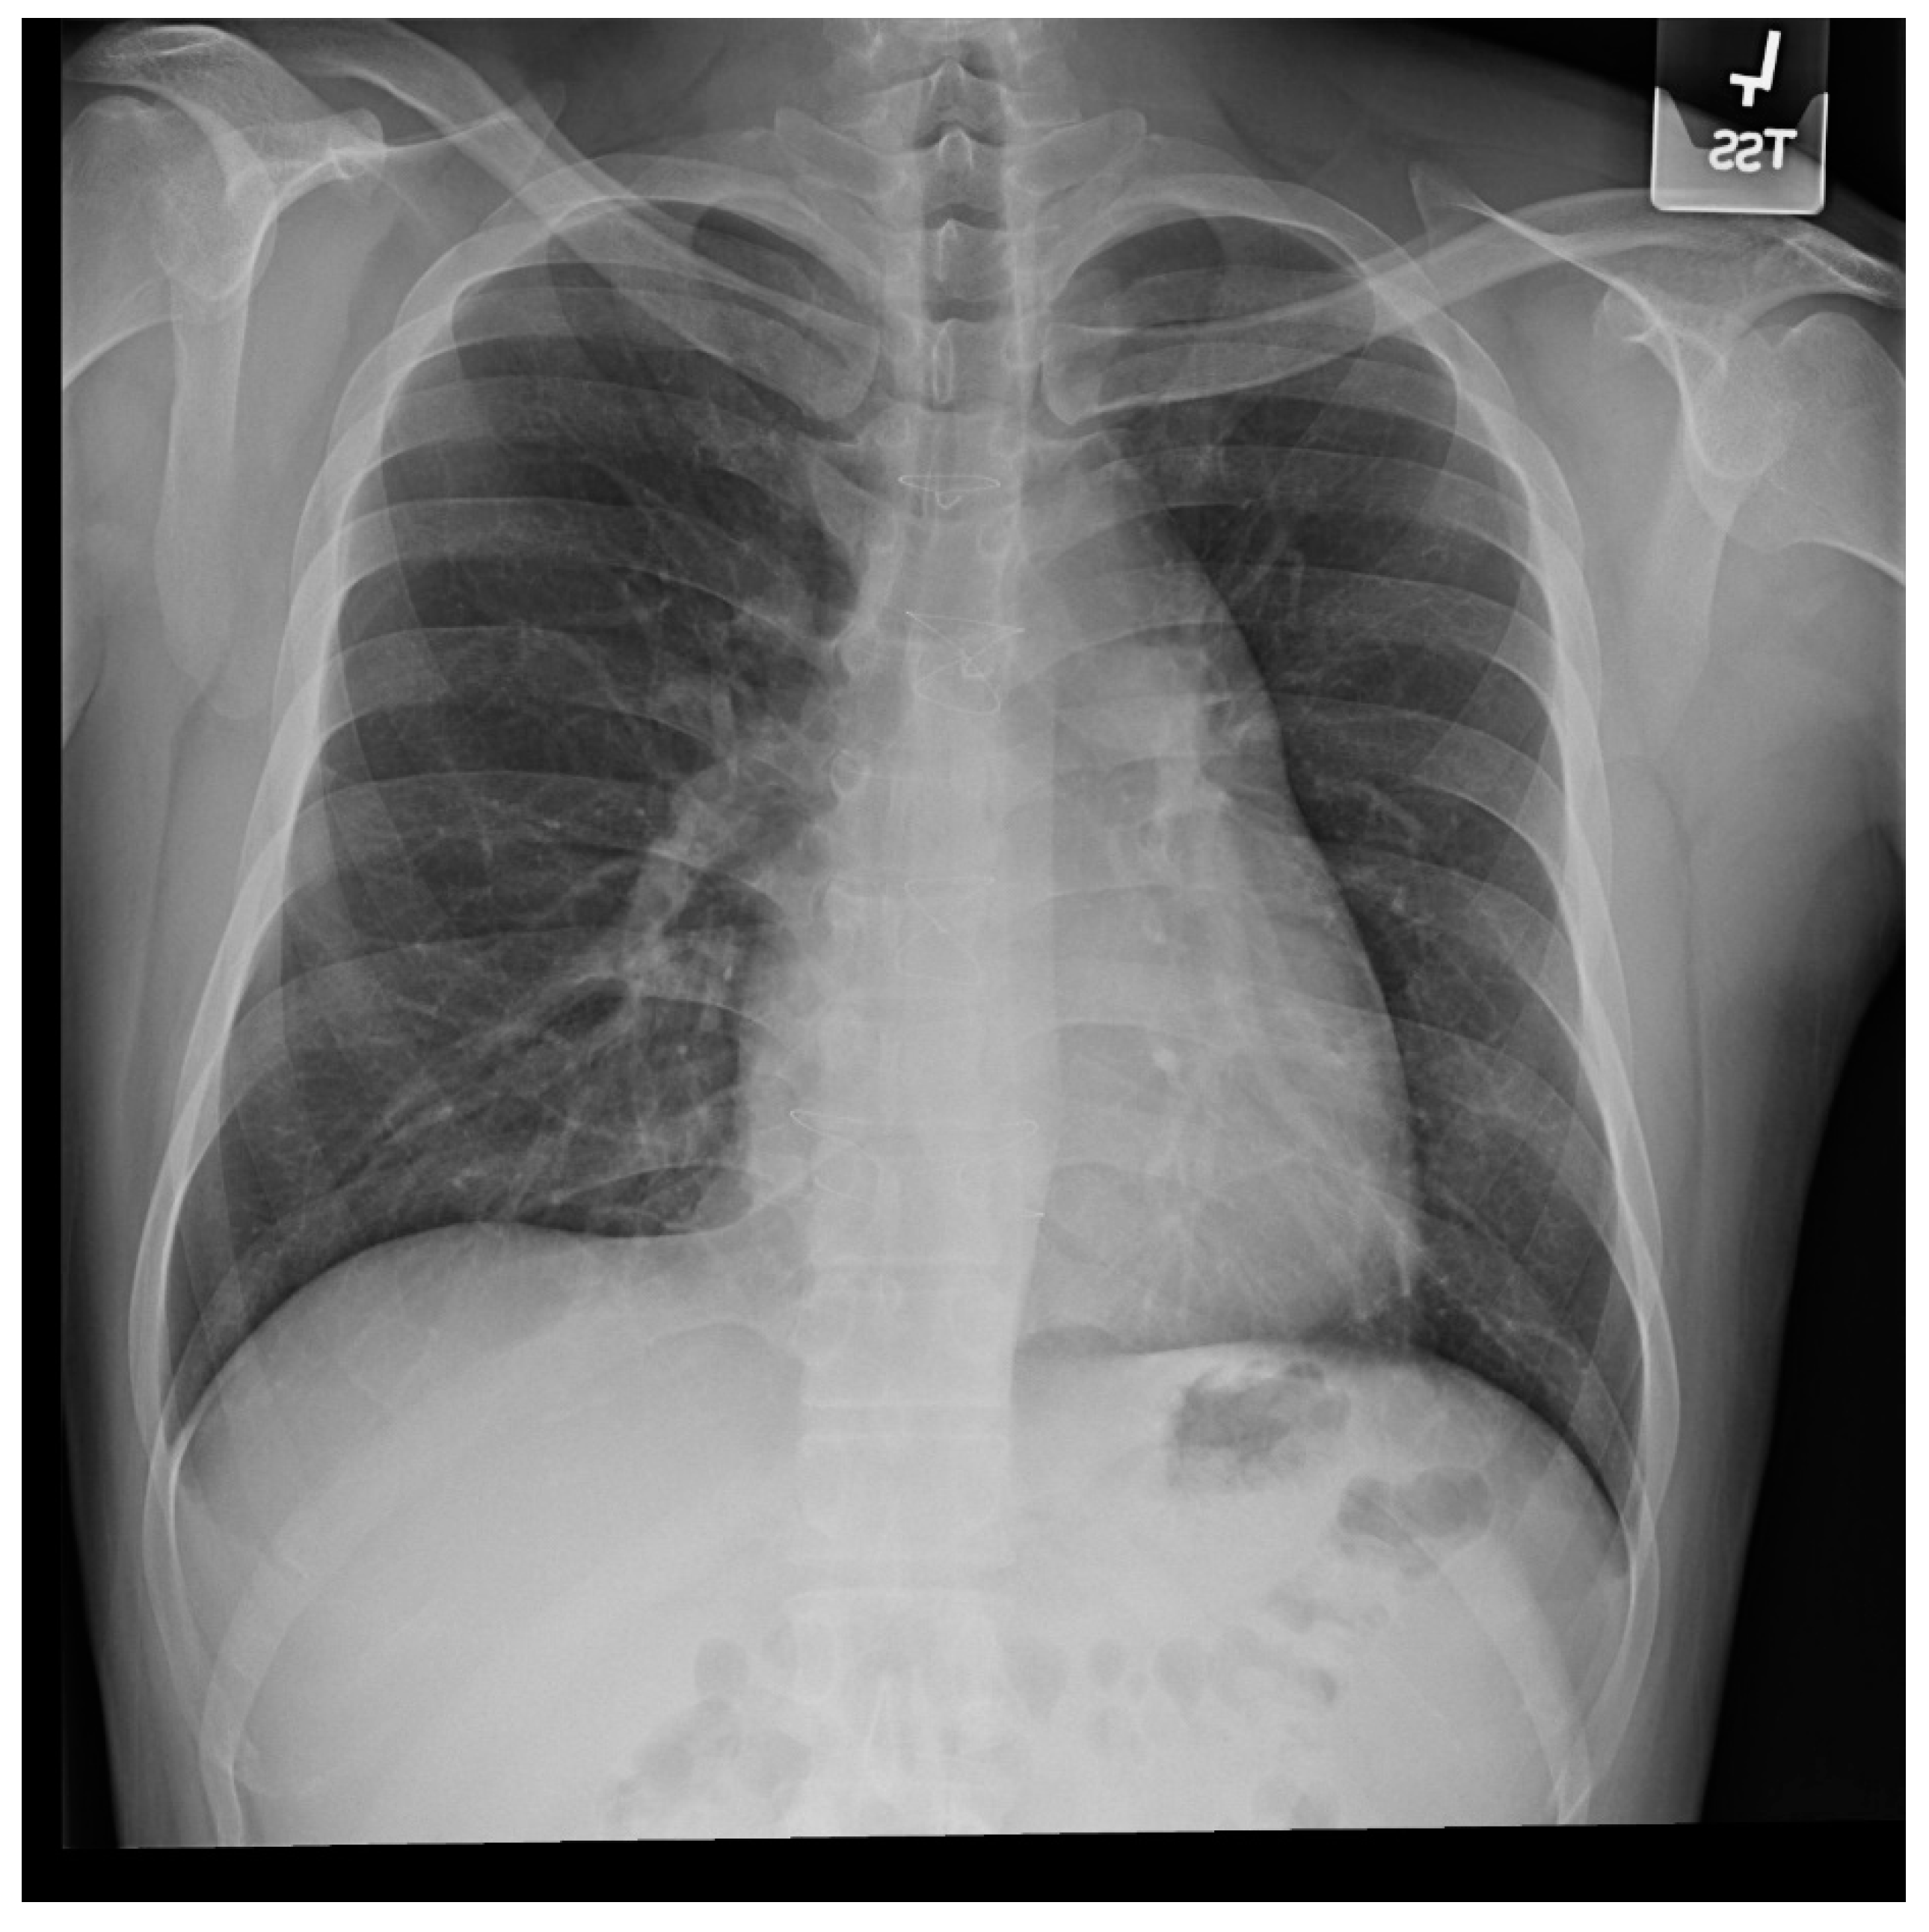

Figure 10.

Posteroanterior chest X-ray of ostium secundum atrial septal defect (OSASD): This is a chest X-ray of a 46-year-old male with an uncorrected OSASD. The image is slightly rotated. There is a good inspiration. The cardiothoracic ratio is increased. The pulmonary trunk is enlarged and there is a lateral rim of calcification. Compared to the enlarged central pulmonary circulation the more peripheral pulmonary vessels are much smaller (called pruning), suggesting pulmonary vascular obstructive disease. The lower right heart border demonstrates right atrial enlargement. The aortic knob is smaller than the pulmonary trunk, indicating a significant left to right shunt.